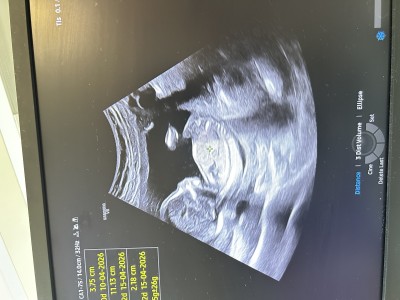

30 Kasım 2025 Hamilelik Dönemi Genel kategorisinde (4 puan) sordu

rica etsem tahminde bulunabilir misiniz 🙏🏻

Kapatılma nedeni: İsim tavsiye veya cinsiyet tahmini gibi soruların sohbet alanında sorulması gerekmektedir. Menüden gebelik dışı konular için ayrılmış alanda konunuzu açabilirsiniz..

Kıza benziyor canım

Erkeğe benziyor nub una gore